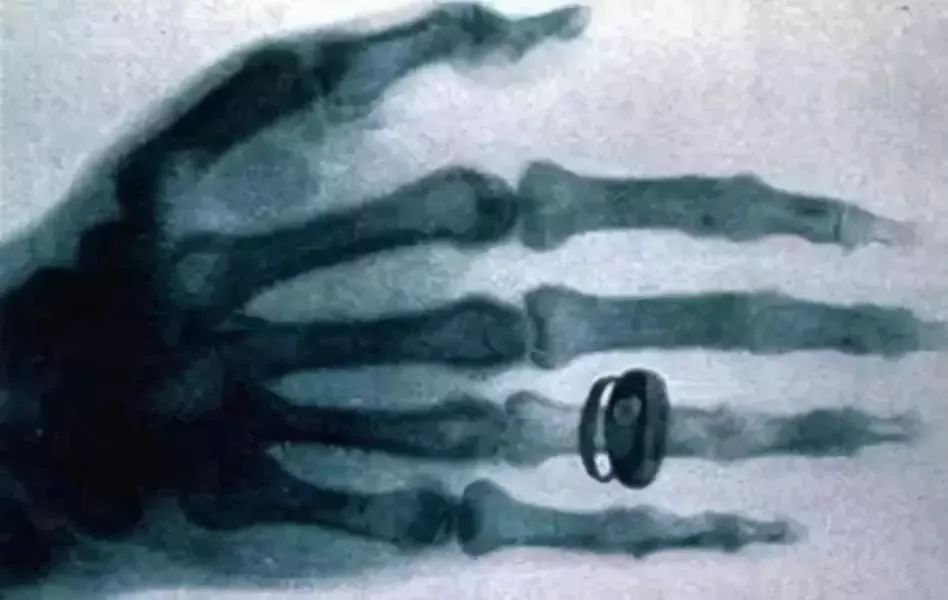

首先,我们来讲讲两枚戒指的故事。

威廉·康拉德·伦琴发现X光的时候,整个伦敦的贵族圈子都开始为这神奇的光沸腾。这光居然能透视伦琴夫人那戴戒指的手。

借着这两枚戒指的故事,我们今天就来聊聊和放射影像检查有关的那些事儿。